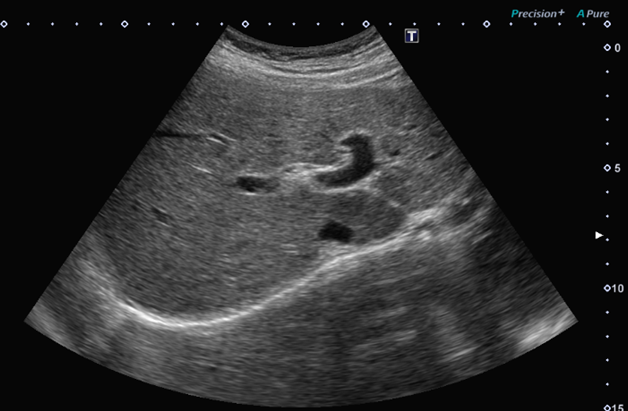

腹部超音波検査

肝臓・胆嚢・膵臓・腎臓などが対象の臓器です。

検査時間20~40分程度。

どんなことがわかる

脂肪肝の程度、胆石、悪性腫瘍の有無など

検査にあたって

食事の制限が生じる検査です。

食事をすることによって、胆嚢が小さくなったり、胃に食物残渣や腸管ガスが多くなり画像の描出が不良になります。

必要に応じて

肝臓内の腫瘍が、通常の超音波検査で存在診断が困難な時や腫瘍の良悪性の鑑別を行う時に、超音波造影剤を用いて検査を行うこともあります。超音波検査で使われる造影剤は副作用が少ないため、腎機能障害がある方でも検査が可能なことが多いです。

写真 腹部超音波検査